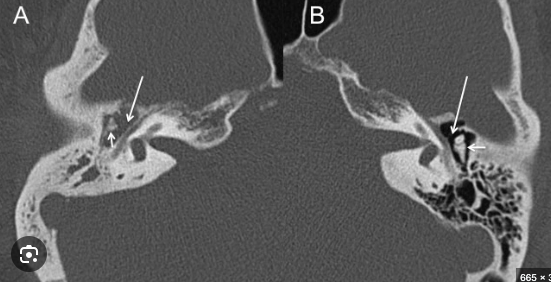

Hallazgos de TC:

• Opacificación de celdillas mastoideas

• Crónico: Esclerodiploico = engrosamiento óseo

Hallazgos en imagen:

RM o TC

• Otitis y mastoiditis

• Masa que destruye hueso

A (afectado): se pierden huesecillos